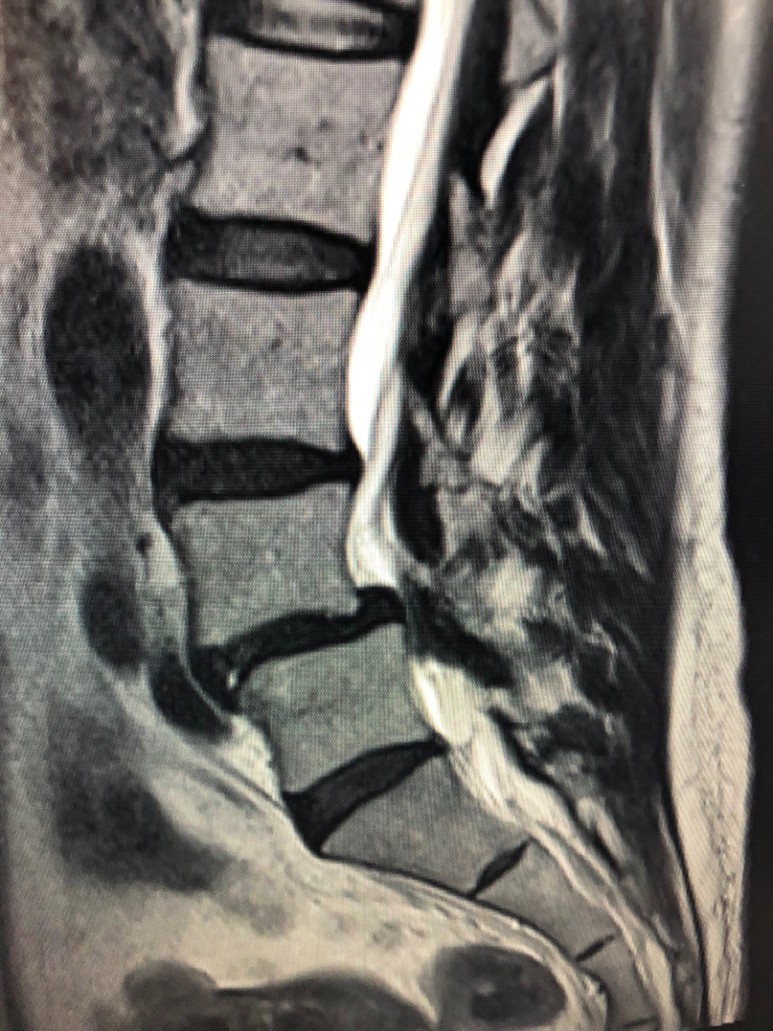

어느 날 다리 저림, 시린 증상이 심해져서 병원에 가서 MRI와 CT 검사를 받았는데 선생님께서 디스크 파열과 척추관협착증 초기를 동반한 척추전방전위증 1기 정도라고 말씀하셨습니다. 알아보니 척추전방전위증 1기라면 척추가 전방으로 약 25% 이내로 밀렸다는 얘기였습니다. 50% 이상 밀리면 척추 고정 유합술을 하는 것이 좋다고 해서 겁이 났습니다. 척추전문병원의 권유대로 디스크 수술(감압수술)을 받고 병원에서 잠시 쉬었다가 일상생활로 복귀하였습니다.

척추전방전위증 MRI 출처 : 지코일 고객제공